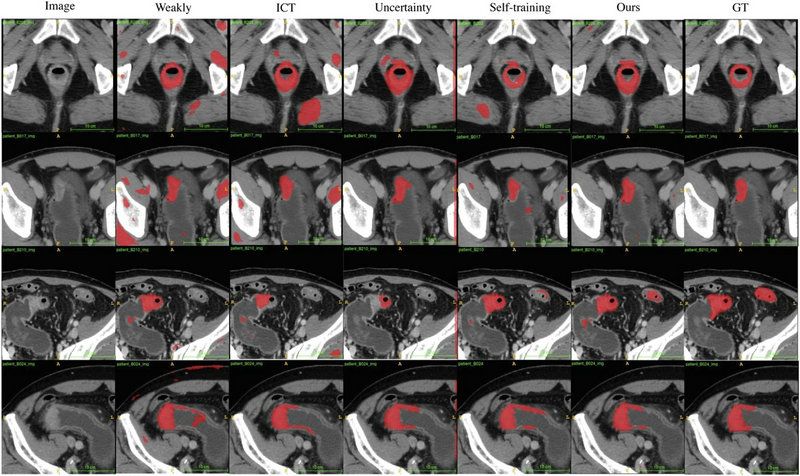

团队利用来自bat365在线中国登录入口附属第六医院和喀地一院的923例有标注结肠癌CT影像和2670例无标注结肠癌CT影像作为SOUSA框架的训练数据集,并利用417例结肠癌CT影像对SOUSA框架进行验证,结果显示其自动分割效果优于现有的弱监督和半监督学习模型。与目前最先进的方法ICT (Verma et al.,2019)、不确定性感知(Yu et al.,2019)和自我训练相比,SOUSA框架在每个数据比率上都达到了最佳性能。此外,当数据集的大小有限时,SOUSA框架的性能甚至与使用密集注释的模型的性能相当。

对肠癌数据集使用不同方法的自动分割结果